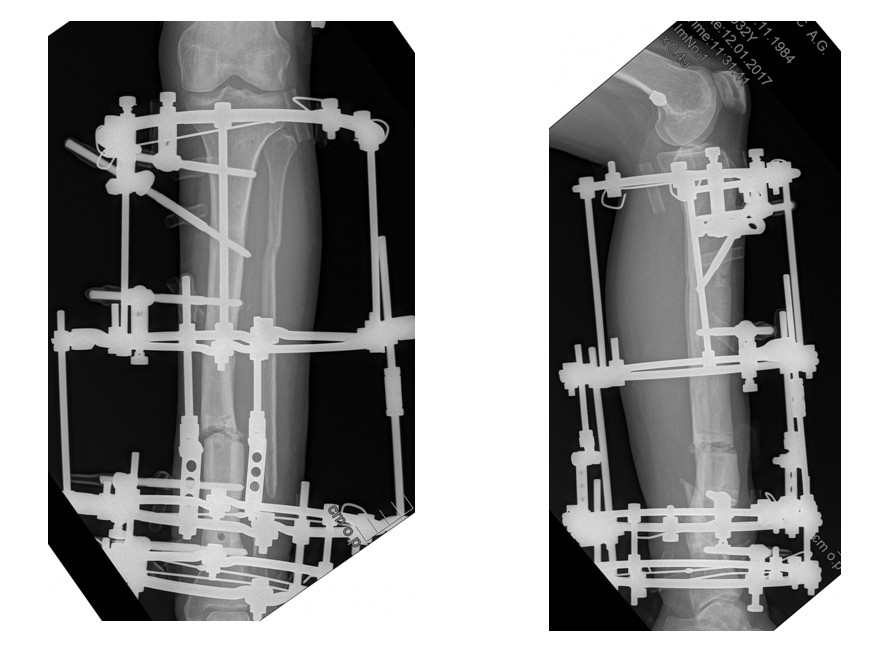

Деформация устранена